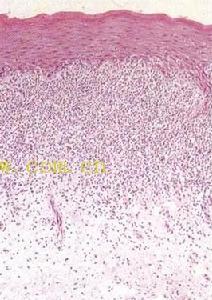

6、組織病理具有特徵性。表皮角化過度,顆粒層呈據灶性楔形增厚,棘細胞不規則增厚,表皮突呈鋸齒狀,基底細胞液化變性,真皮上部淋巴細胞呈帶狀浸潤,真皮乳頭層可見膠樣小體及嗜黑素細胞黑素細胞是一種動物細胞,帶有黑色素或其他類似的色素,通常位於皮膚的表層與眼鏡的葡萄膜中,恆溫動物的黑色素細胞又稱為黑素細胞。黑色素細胞的代謝若是受到破壞或抑制就會產生一些疾病,如遺傳疾病白化症與一種稱為黑色素細胞瘤的癌症。此外皮膚毛髮眼睛的顏色以及黑痣雀斑等皮膚上的斑點都與黑素細胞有關。